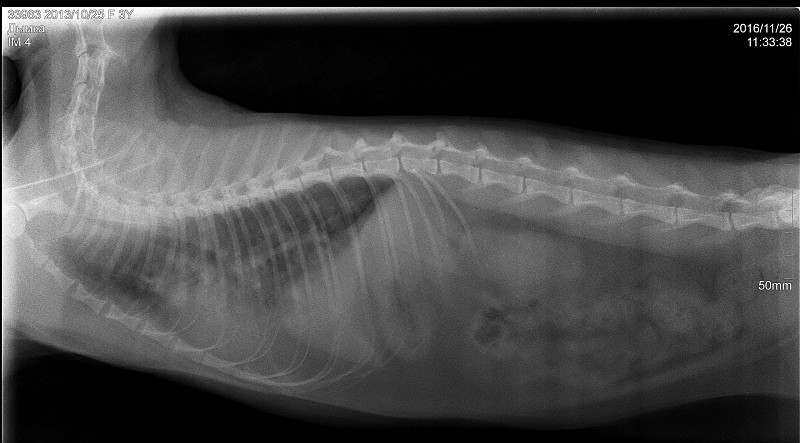

В клинике собаке сделают рентген, который подтвердит или опровергнет отек легких, а также проведут осмотр собаки, прослушают ее и выполнят ряд лабораторных исследований.

Для диагностики отека легких у собак используются такие методы, как аускультация, рентгенография грудной клетки или ультразвуковое исследование, также требуется анализ крови. Электрокардиограмма, анализ мочи и измерение кровяного давления — другие важные тесты, позволяющие выяснить, есть ли у вашей собаки отек легких.

Если состояние вашего питомца стабильное, можно выполнить рентгенографию грудной клетки, положив собаку на спину. На этой рентгенограмме могут быть признаки отека легких, такие как повышенная интерстициальная или альвеолярная непрозрачность. У собак, страдающих кардиогенным отеком легких, также могут наблюдаться кардиомегалия и расширенные легочные вены.

Рентгеновские снимки являются основным инструментом для диагностики отека легких, поскольку они выявляют жидкость внутри легких собаки. Рентген также может выявить увеличенное сердце или другие аномалии сердечной мышцы.